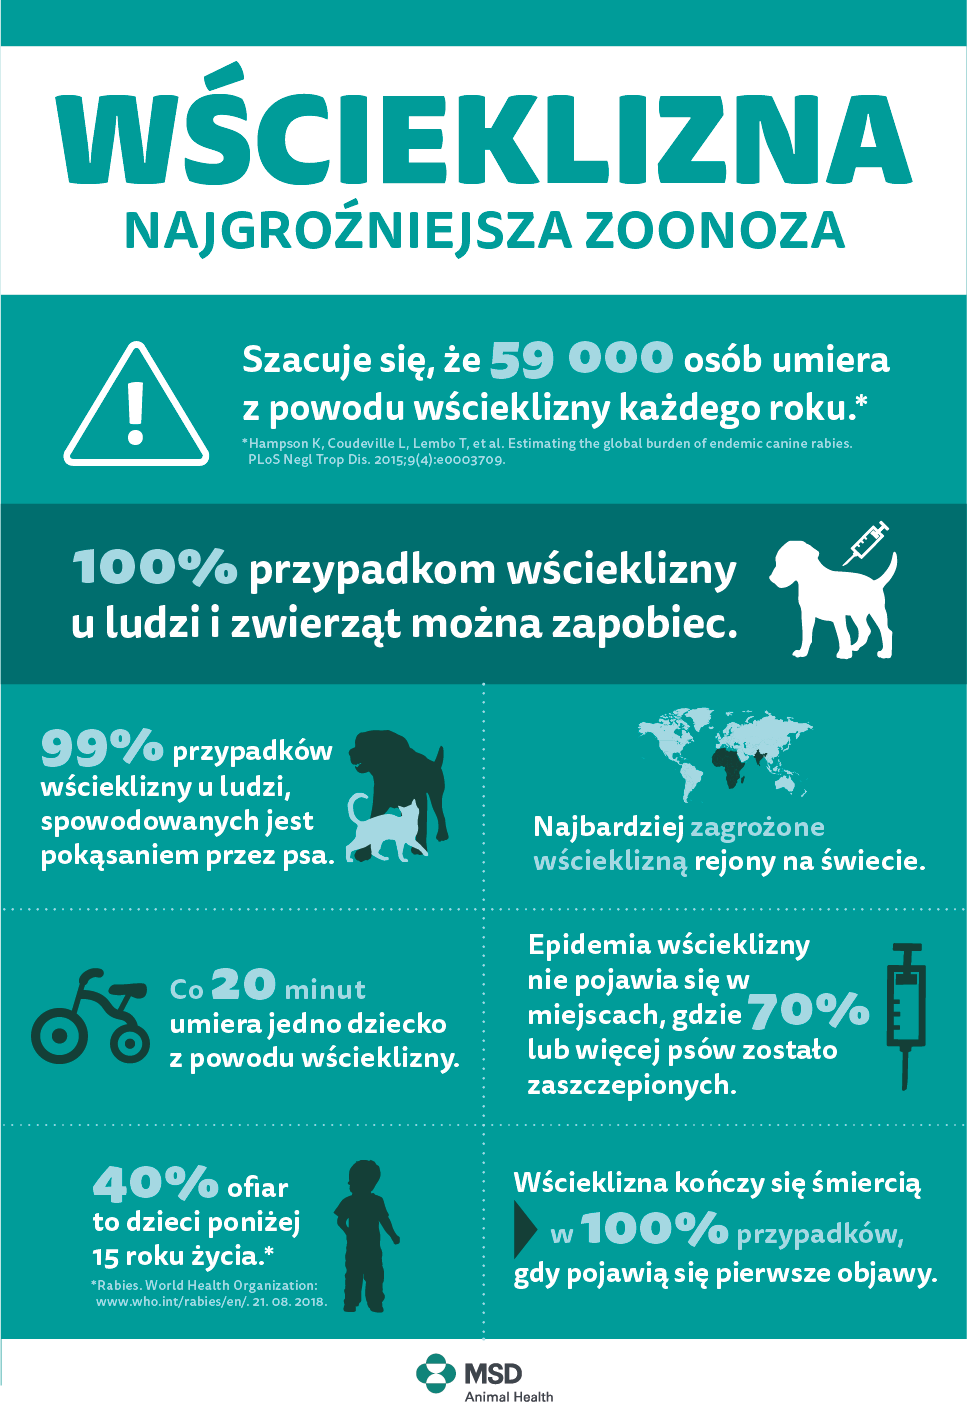

Wścieklizna występuje najczęściej w Afryce i Azji. Globalizacja powoduje, że choroba może łatwo wrócić do Europy. 99 proc. przypadków wścieklizny u człowieka spowodowanych jest pogryzieniami przez psy. Dlatego musimy przestrzegać obowiązkowego programu szczepień w naszym kraju – przestrzegają eksperci.

Według danych Światowej Organizacji Zdrowia, ponad 99 proc. przypadków wścieklizny u ludzi, spowodowanych jest pogryzieniem przez psy. Mimo, że istnieją sprawdzone metody eliminujące zagrożenie tej zoonozy, ok. 59 tys. osób umiera co roku z powodu wścieklizny. Ponad 95 proc. tych zgonów ma miejsce w Afryce i w Azji. Mimo, że główne zagrożenie występuje poza Europą, według statystyk w Środkowo-Wschodniej części kontynentu, zwierzęta domowe i dzikie nadal są narażone na wściekliznę.

Każdy europejski kraj ma swój własny program szczepień przeciwko wściekliźnie dla psów. Częstotliwość szczepień zależy od poziomu ryzyka, jakie znajduje się w danym kraju. W Polsce lub na Węgrzech właściciele psów muszą szczepić je co roku, aby zapewnić bezpieczeństwo swojemu pupilowi oraz pozostałym ludziom i zwierzętom w kraju. Chociaż częste szczepienia przeciwko wściekliźnie dla kotów nie są obowiązkowe w każdym kraju (mimo, że również są narażone na wściekliznę), lekarze weterynarii zalecają, by koty także miały szczepienia profilaktyczne.

– Dobrze zaplanowany program szczepień jest potrzebny, aby zapewnić zdrowie zwierzętom dzikim i domowym, co przyniosłoby znaczące korzyści dla zdrowia publicznego. Celem jest szczepienie ponad 70 proc. psów przeciwko wściekliźnie na obszarach enzootycznych. Jest to poziom umożliwiający ograniczenie rozprzestrzenienia się choroby wśród psów, a tym samym wśród ludzi. W tym celu konieczne jest szczepienie psów i kotów na całym świecie, abyśmy mogli zapewnić bezpieczeństwo naszym zwierzętom, a także sobie – zwraca uwagę ekspert.